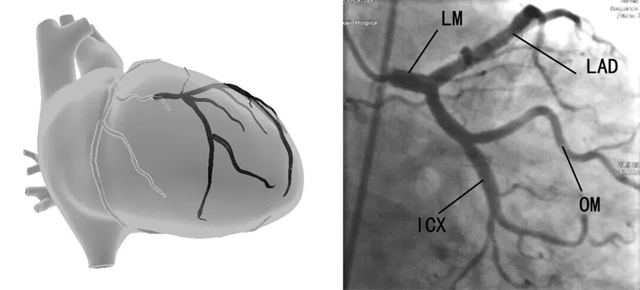

冠状动脉CT/冠状动脉造影,二者都是通过在冠状动脉内注入造影剂,借助X透视的指导从而了解供应心脏血管是否有堵塞,冠状动脉的通畅程度,是诊断冠心病的金标准。

同一患者心电图、心脏彩超、冠脉造影对比图

高度怀疑冠心病患者,最好选择直接做有创的冠脉造影,在何种情况选择冠脉CT或冠脉造影,见下表。